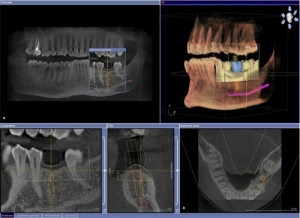

Jelenleg ortopantomogramma végezzük digitális eszközök. A kép van nyomtatva a film át bármely digitális közegben, átküldi az interneten, és tárolja a klinikai adatbázis. Ezen kívül a fényképet át a képernyőn, ahol az orvos hozhat érdekes helyszínek és egy részletes tanulmányt őket.

Digitális ortopantomogramma egy átfogó diagnózist. A helyes dekódolást azonosítani bármely patológia, még a kezdeti szakaszban.

- Magas képminőség (megfelel a nemzetközi szabványoknak). Nagy felbontású orto - képekkel mutatja még kisebb változtatásokat és patológia, amely lehetővé teszi, hogy diagnosztizálják a betegséget korai stádiumban. Az orvos képes böngészni a szükséges területeken a képernyőn növelésével vagy csökkentésével a képet.